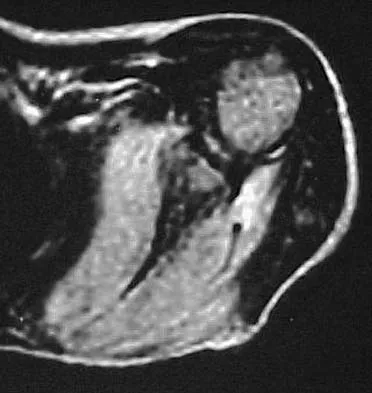

Figure 50 shows the MRI scan of a 20-year-old female college soccer player with knee pain. What is the most likely diagnosis?